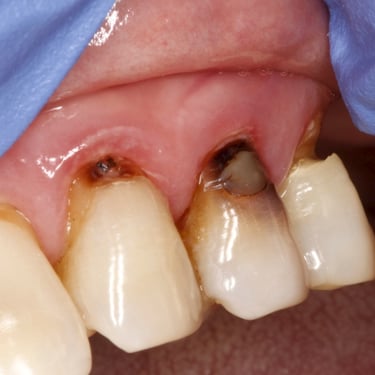

Caries Radicular

La caries radicular es la descomposición del cemento y la dentina en la raíz del diente, común en personas mayores con recesión gingival.

Los pacientes pueden experimentar sensibilidad y dolor en la raíz expuesta.

El tratamiento incluye la eliminación de la caries y la restauración de la raíz. La prevención incluye una buena higiene oral y el uso de flúor.